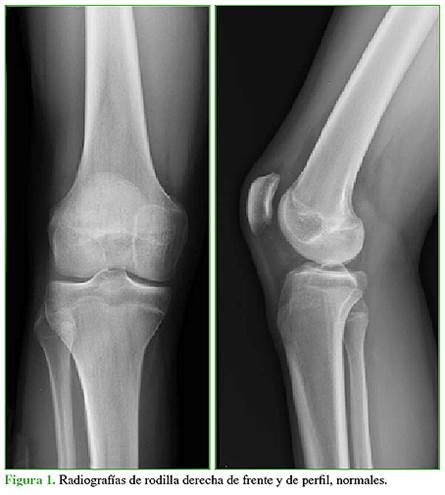

Varón de 18 años que consulta por gonalgia después de practicar actividad física, sin un antecedente de trauma. En el examen físico, no refiere dolor durante las maniobras dinámicas ni palpatorias. Se solicitan radiografías de rodilla de frente y de perfil, y se completa con una resonancia magnética sin contraste.

En las radiografías, no se identifican lesiones aparentes (Figura 1). En la resonancia magnética, se puede observar un importante edema en el cóndilo femoral externo, con compromiso de los sectores metafisario y epifisario, sin lesión del cartílago de crecimiento, visible preferentemente en las secuencias sensibles a los líquidos y con supresión grasa (STIR) (Figura 2A).